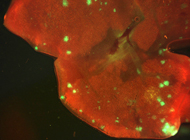

图片说明:侵略性的乳腺癌细胞(荧光点)转移到了小鼠的肺部

随后,研究小组将能够制造miR-10b的乳腺癌细胞移植入幼年雌鼠的乳腺区域。6周后,这些细胞开始散布到机体不同的组织中,比如肺部。而与此相比,非转移癌细胞只会导致小鼠产生乳腺癌,并不会扩散开来。